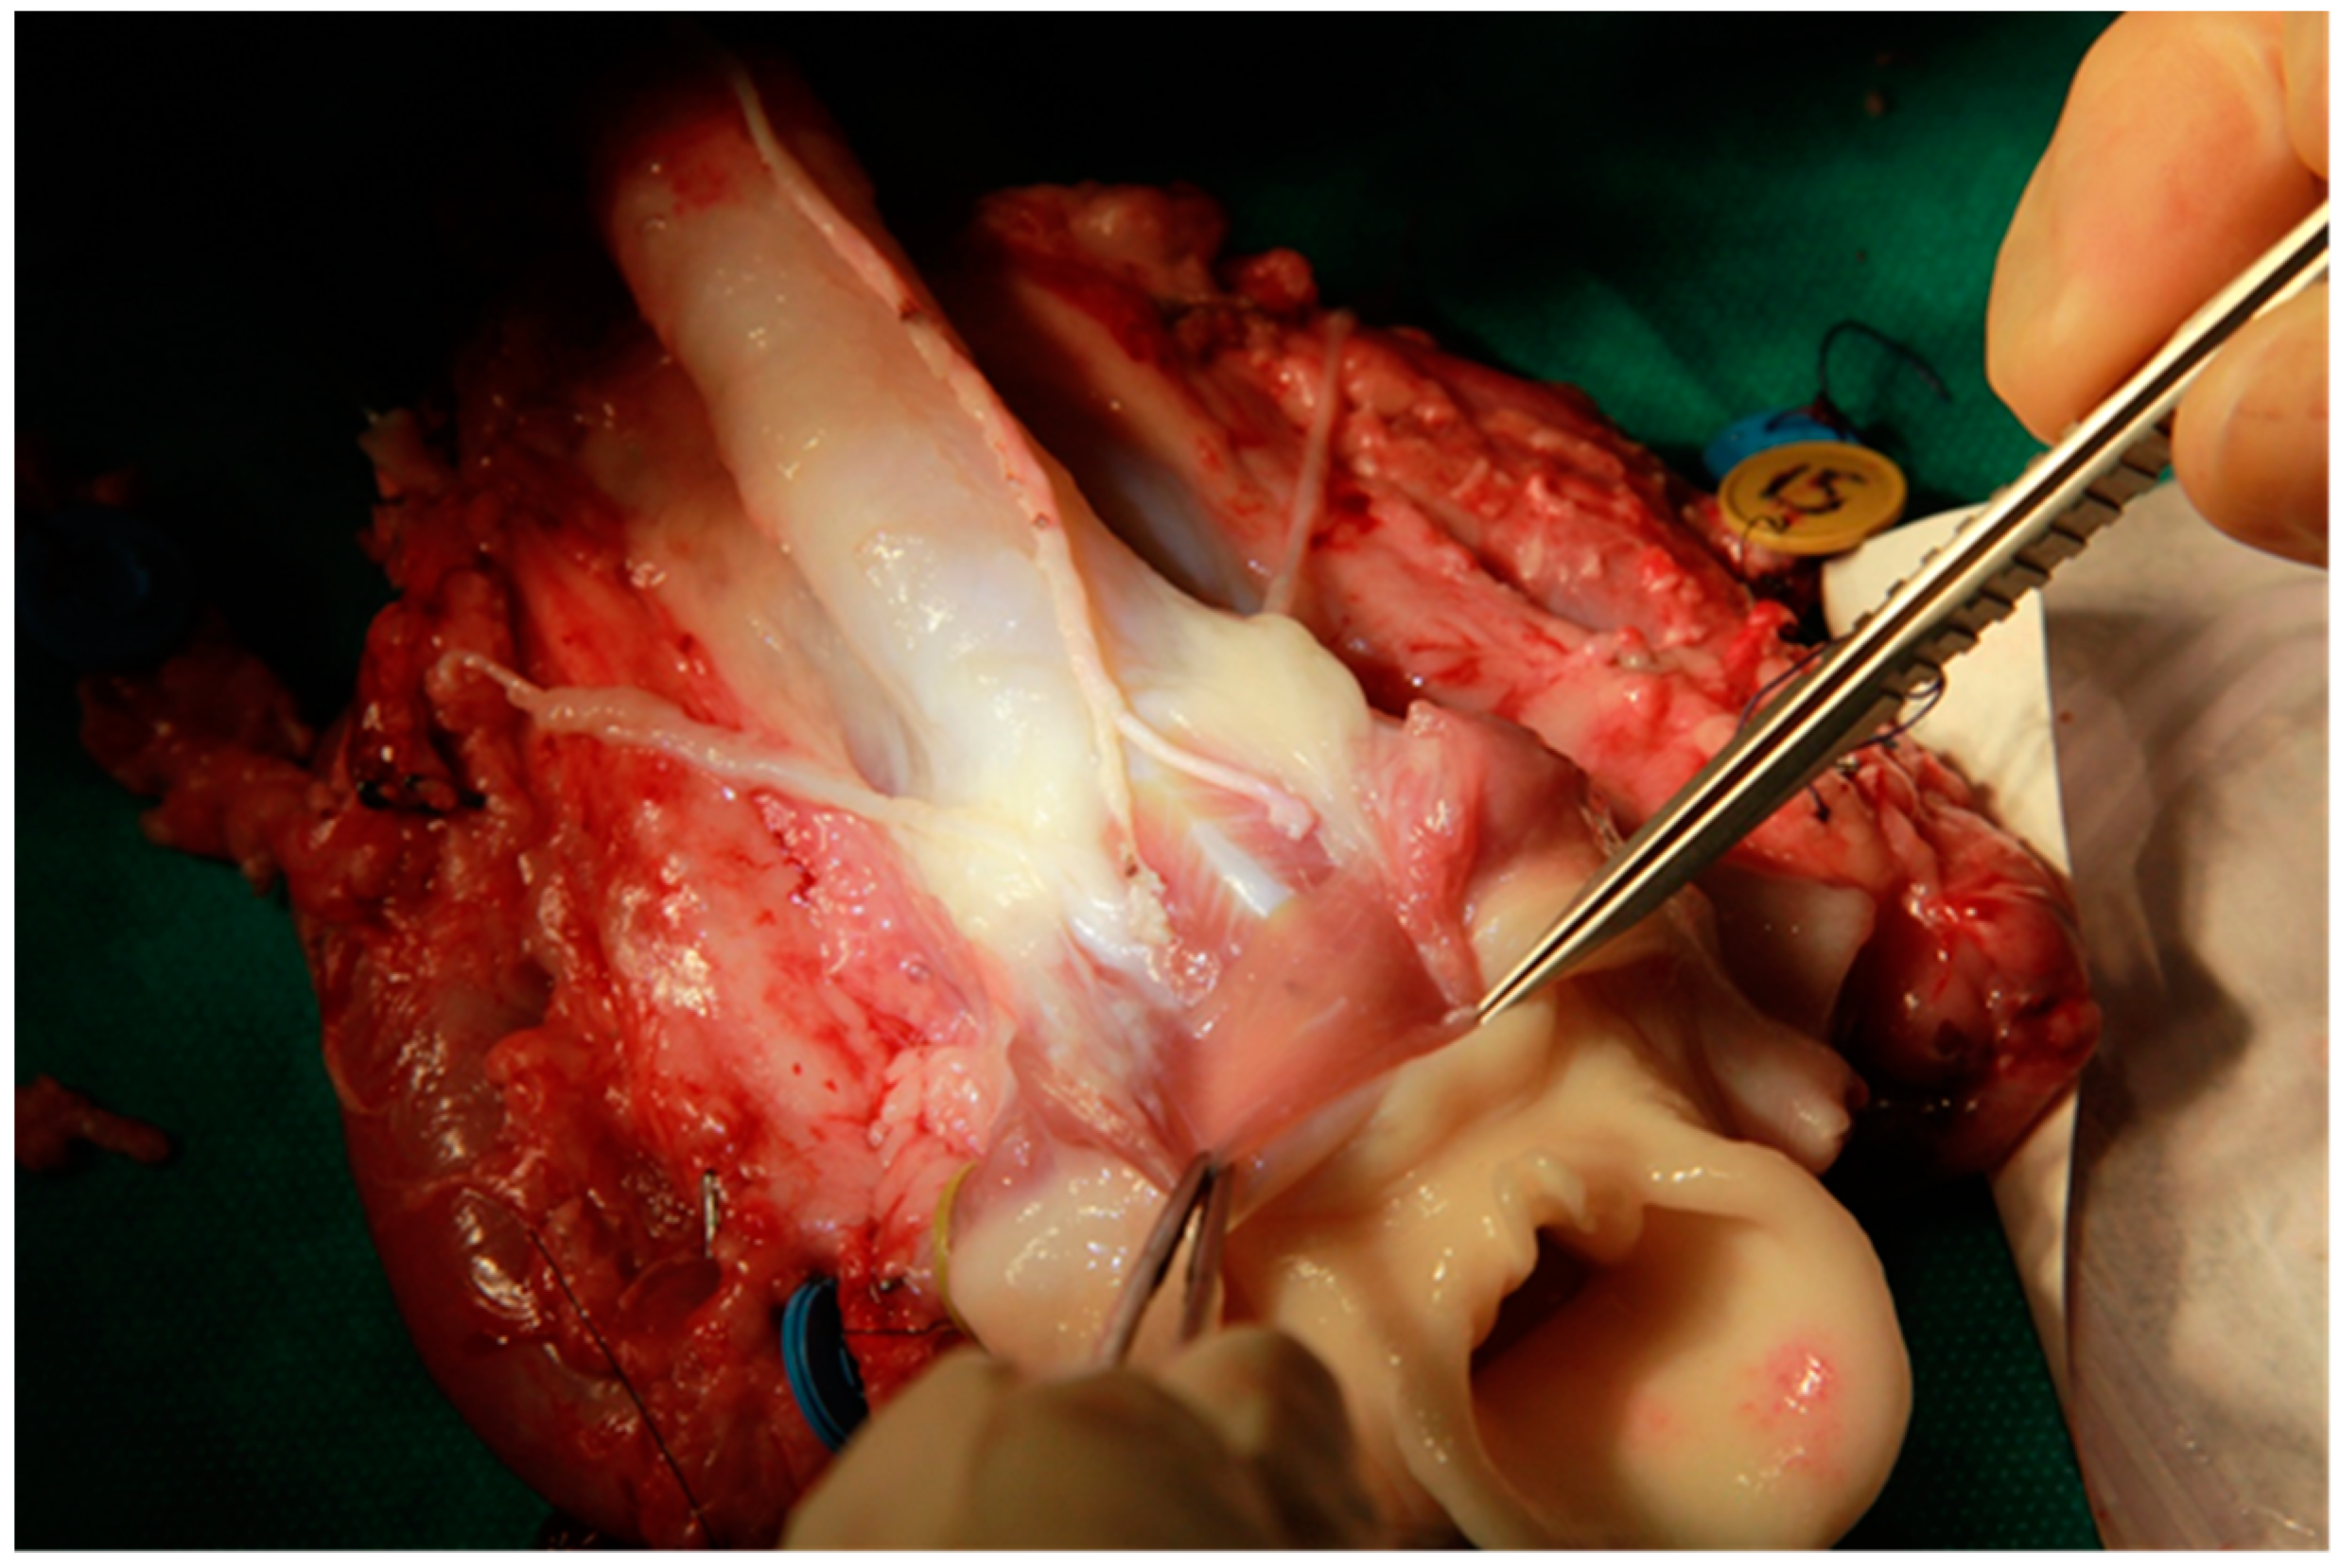

2.1. Removal of the Graft

2.2. Preparation of the Graft